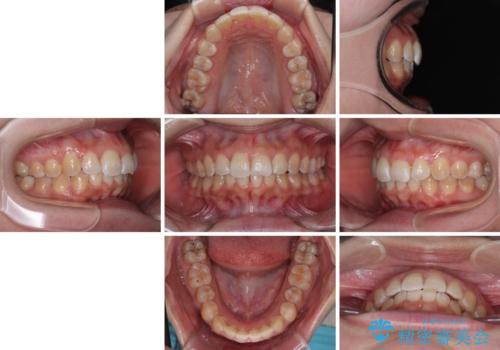

前歯のデコボコをインビザライン矯正で綺麗に改善

- 上下前歯のデコボコを気にして来院された患者様です。

全体的に叢生は軽度であったため、インビザラインにて矯正治療を行うこととしました。

舌の突出癖改善がうまくいかず、途中で舌小帯の切除を行いました。

気になる段差を納得いくまで改善させたため、治療期間は長くなりましたが、綺麗な仕上がりとなりました。